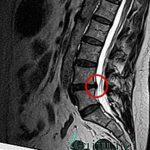

Врач ставит точный диагноз только после проведения инструментального обследования. Допускается УЗИ, но лучше всего пройти МРТ. Делается это для того, чтобы отличить грыжу от миогелеза. При этом заболевании характерно появление нескольких припухлостей на мышце, болит вся она целиком.